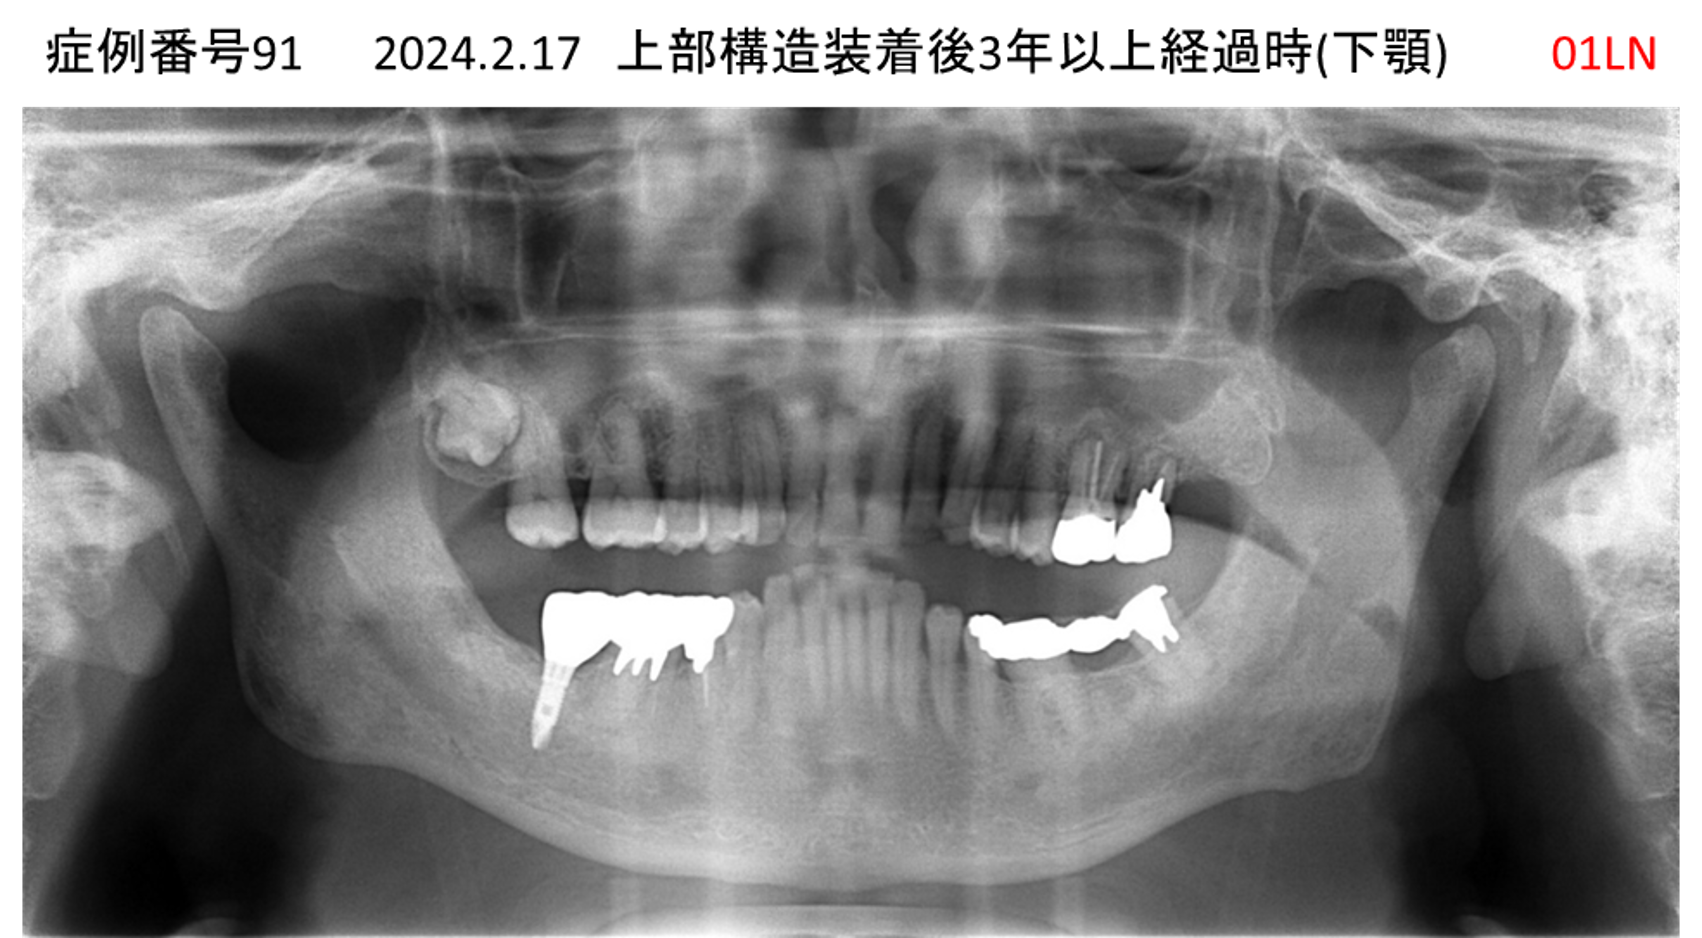

全く噛めない患者様のインプラント症例

| 治療名称 |

インプラントAGC |

| 治療費用 |

860万円+税 |

| 治療期間 |

12か月 |

| 患者さんの症状(主訴) |

全く噛めない、ごはんが後もに食べられるようになりたい、人前で口元を隠したくない |

| 治療内容 |

サイナスリフト、GBR、インプラント、AGC |

| 治療結果 |

しっかり噛めて踏ん張ることができる。食べ物をを選ばなくて済む、何でも食べられる、体重が増えた。見栄えがきれいすぎて自分じゃないみたい |

| 治療の注意点(リスク/副作用) |

インプラントが壊れたら再治療が必要 |